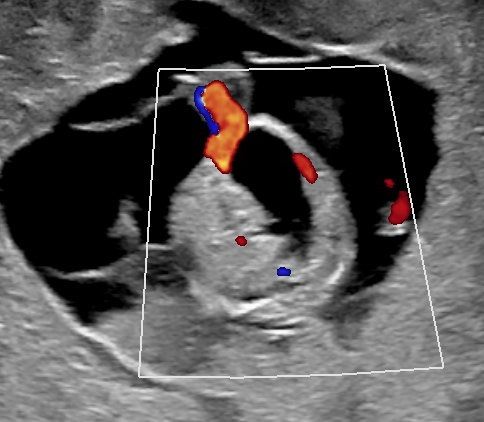

Sonoanatomie, Biometrie, Hinweiszeichen & Diagnose von Entwicklungsstörungen, Kasuistiken, ausreichend Zeit für Diskussionen, Fallbeispiele aus der Praxis (Quiz)